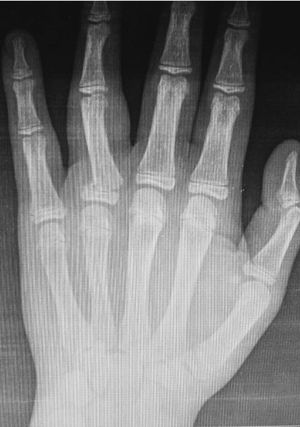

What do you see 😉❓

4th proximal phalanx fracture

4 th proxumal phalanx fracture....in.its proximal end